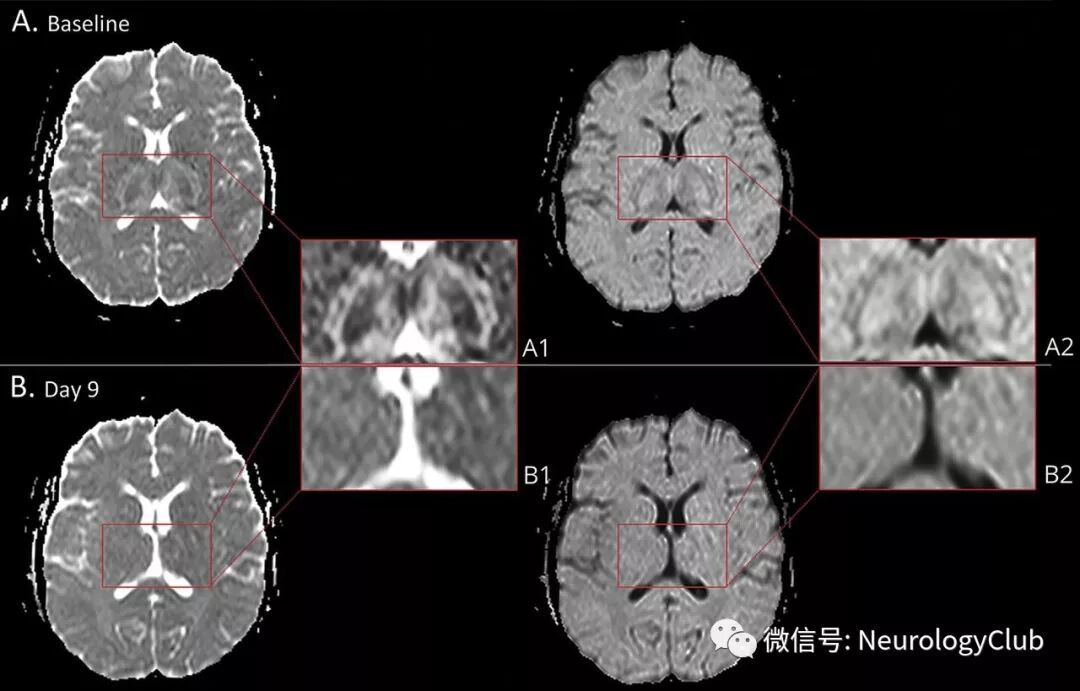

(图1:A:入院时MRI提示脑桥[A.a-A.b]T1WI和T2WI低信号,以及双侧丘脑[A.c-A.d]T1WI低信号和T2WI高信号,证实为出血性坏死;B-C:复查MRI可见脑桥[B.a和C.a:T1WI;B.b和C.b:T2WI)和丘脑病变[B.c和C.c:T1WI;B.d和C.d:T2WI]逐渐好转)

(图2:A:入院时,ADC和DWI可见双侧丘脑靶样病灶和水肿;B:第9天,ADC和DWI可见病灶较前消退)